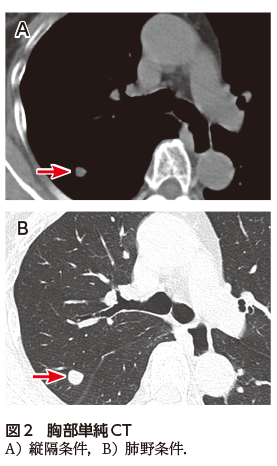

• A1:胸部単純X線写真で右中肺野に結節影を認める(図1).

胸部単純X線写真では右中肺野に右第7肋骨に重なって楕円形の結節影を認めた(図1).胸部CTでは右上葉S2の葉間胸膜直下に13 mmの境界明瞭な円形の結節を認めた.内部の濃度は不均一で,血管収束像や分葉状の辺縁は認めなかった(図2A,B).PET-CTでは同部位にSUVmax 12.56のFDG集積を認めた(図3).腫瘍マーカーは正常であった.CTでbronchus sign陽性の気管支は存在しなかったため,気管支鏡検査は施行せず,肺がんcT1bN0M0 StageⅠA2疑いとして診断・治療目的で右肺S2区域切除術を施行した.病理検査では多数の多核巨細胞を含む組織球が集簇した肉芽腫性の病変を認め,一部に変性壊死を起こしていた.Grocott染色で組織球に貪食される無数の酵母状真菌が観察され,肺クリプトコッカス症の診断となり,手術で病変は切除できているので無治療も選択肢だったが,患者と相談し,フルコナゾールの内服を開始した.